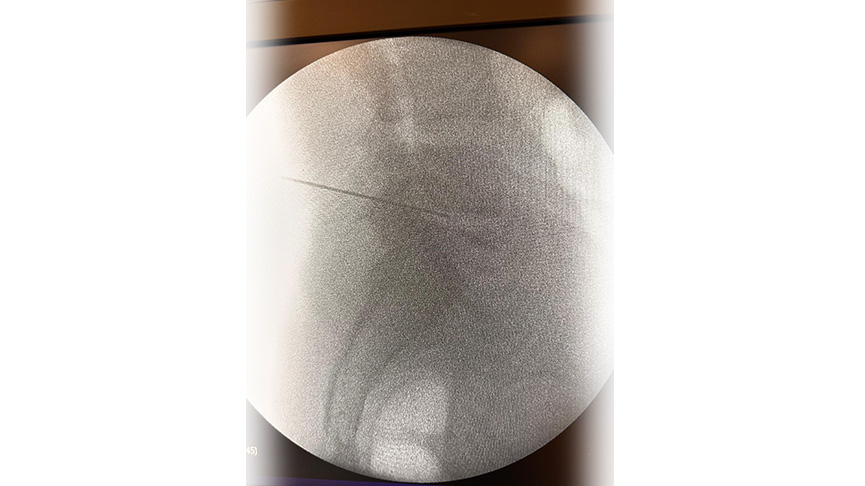

Yöntem: Uygulama lokal ve/veya sedayon anestezi altında yapılır. İşlem öncesinde skopi denilen anlık röntgen çekimi yapan cihaz ile doğru nokta belirlenir

İğne ve Ekipman: Daha sonrasında özel bir iğne veya kateter kullanılarak işlem yapılır. İğne, diskin iç kısmına yerleştirilir ve Plazma RF enerjisi ile işlem yapılır.

Hedef Bölge: Tedavi, fıtıklaşmış diskin belirli bir noktasına yapılır. Bu nokta, ağrıyı başlatan sinirlere baskıyı azaltacak şekilde seçilir.